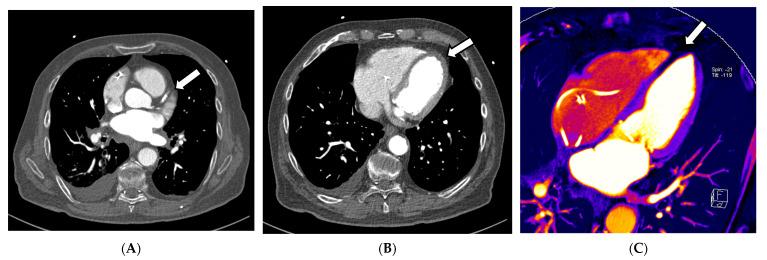

This article describes the technical principles and clinical applications of dual-energy computed tomography (DECT) in the context of cardiothoracic imaging with a focus on current developments and techniques. Since the introduction of DECT, different vendors developed distinct hard and software approaches for generating multi-energy datasets and multiple DECT applications that were developed and clinically investigated for different fields of interest. Benefits for various clinical settings, such as oncology, trauma and emergency radiology, as well as musculoskeletal and cardiovascular imaging, were recently reported in the literature. State-of-the-art applications, such as virtual monoenergetic imaging (VMI), material decomposition, perfused blood volume imaging, virtual non-contrast imaging (VNC), plaque removal, and virtual non-calcium (VNCa) imaging, can significantly improve cardiothoracic CT image workflows and have a high potential for improvement of diagnostic accuracy and patient safety.

本文介绍了双能计算机断层扫描(DECT)在心胸成像中的技术原理和临床应用,重点关注当前的发展和技术。自DECT问世以来,不同供应商开发了不同的硬件和软件方法来生成多能量数据集,并针对不同的感兴趣领域开发和临床研究了多种DECT应用。最近文献报道了DECT在各种临床环境中的益处,如肿瘤学、创伤和急诊放射学,以及肌肉骨骼和心血管成像。诸如虚拟单能量成像(VMI)、物质分解、灌注血容量成像、虚拟非增强成像(VNC)、斑块去除和虚拟无钙(VNCa)成像等先进应用,可以显著改善心胸CT图像工作流程,并具有提高诊断准确性和患者安全性的巨大潜力。